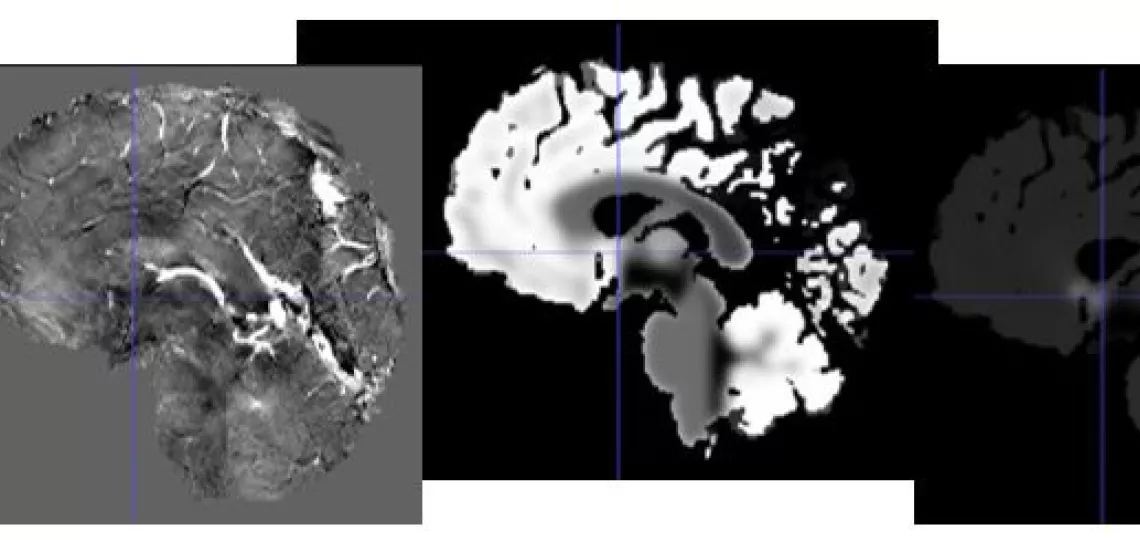

MR images of the brain, from left: TOF, SWI, fractional blood volume, mean vessel density, mean vessel radius.